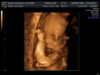

Dzidzia rośnie...trzeba się cieszyć:-)Od poczatku ciąży przytyłam 5,5kg patrząc na wagę rano na czczo. Wieczorem w ciuchach (np ważąc się u pani dr) potrafię ważyć ponad 2 kg więcej...Mnie przybyło teraz w 4 tyg 4 kilo. Nie wiem dlaczego, bo się nie obżeram, ćwiczę, nawet słodyczy zaczęłam sobie odmawiać, a tu taki klops...